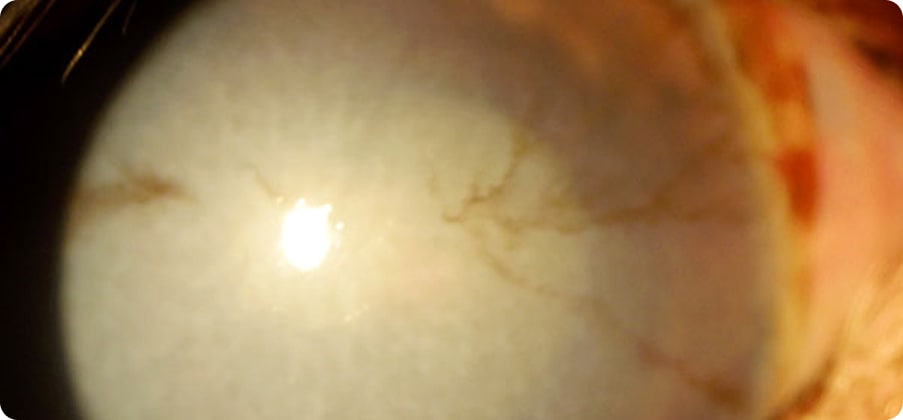

角膜は透明性を維持するために、水などを調節するポンプ機能を有しています。角膜水腫はそのポンプ機能が失われた場合に発症し、角膜が白く濁る事が特徴的です。角膜に傷ができた時、緑内障、ぶどう膜炎などでポンプ機能が失われる事が多いです。

角膜が白く濁り(浮腫・結晶)角膜が白く濁り(浮腫・結晶)、痛みがない、両眼で起こりやすい事が特徴的です。遺伝によるものや免疫が関与することがあり、キャバリア、シェルティ、ビーグル、チワワ、プードルなどで発症しやすいです。